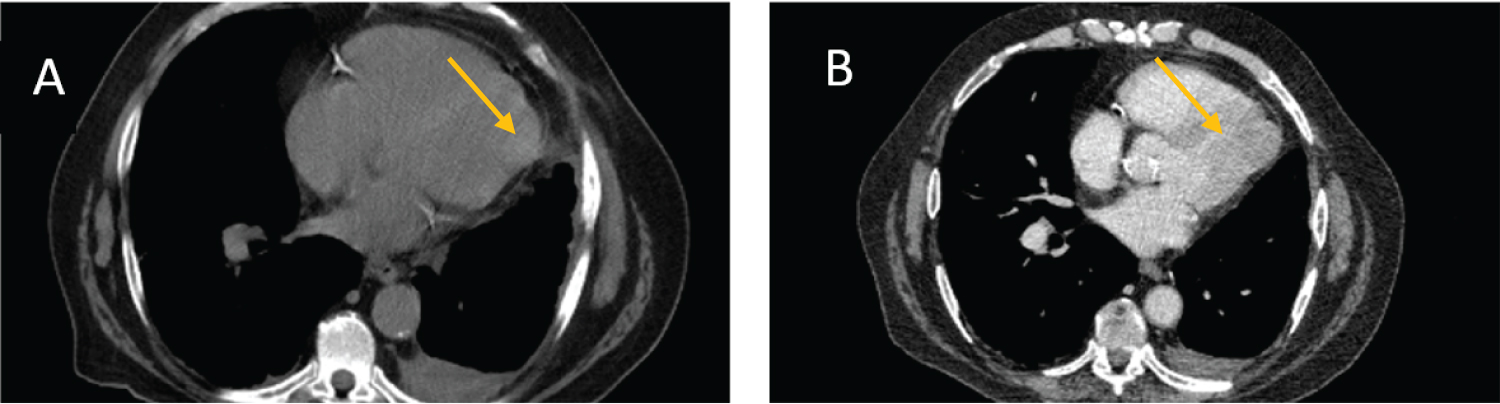

Cardiac MRI (Figure 2) demonstrated a mass in the anterolateral wall measuring 19.7 × 32.8 × 39 mm. The mass was described as hypointense on T2 weighted images with isointense to slightly hypointense on T1 weighted imaging sequences. For the mass, there was limited first pass perfusion and profound, extensive late gadolinium uptake. These findings supported a diagnosis of a large cardiac fibroma. The calculated LV ejection fraction was estimated at 50%. There was "possible compression of the apical anterolateral wall from the mass that may impact diastolic relaxation". The calculated RV ejection fraction was 44%. On late gadolinium imaging, there was no myocardial infarction noted.

Figure 2: Magnetic Resonance Imaging portraying the cardiac fibroma. A) T1; B) fat saturated T1 and C) T2 are depicted. View Figure 2